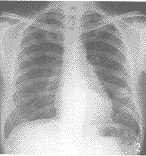

图1 右肺第5、6后肋间散在浸润性病变,左肺第8、9后肋间可见直径约2.5cm椭圆形肿块。 图2 右肺清晰,左肺下部椭圆形肿块仍存在,大小无明显变化。 图3 左侧位胸片,第9胸椎高度部位可见浅淡的片状阴影。 图4 CT片:左外基底段有直径2cm块状阴影,后侧边缘较清晰,前侧边缘毛糙,密度均匀。